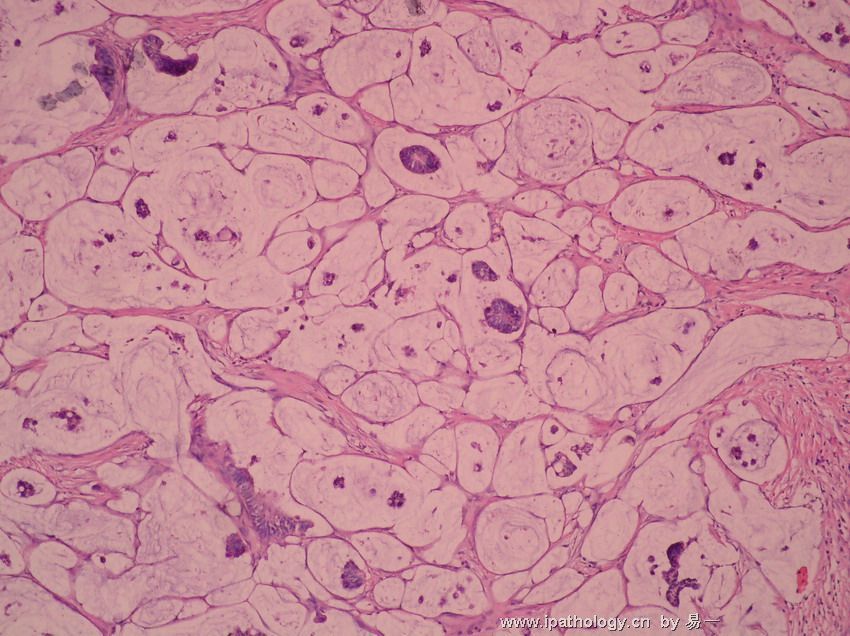

它可使机体发生慢性输卵管炎与输卵管积水、输卵管卵巢炎及输卵管卵巢囊肿、慢性盆腔结缔组织炎。慢性盆腔炎的症状特点是:其病慢,病程长。全身症状多不明显,可有低热,易感疲乏,伴下腹坠腰痛等。检查时发现,子宫常呈后位,活动受限,或粘连固定。慢性盆腔炎的主要鉴别诊断有:子宫内膜异位症和卵巢癌。